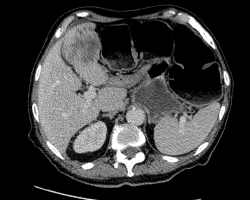

223. Artériopathie oblitérante de l'aorte, des artères viscérales et des membres inférieurs ; anévrysmes

Thrombose de l’aorte

2 août 2017